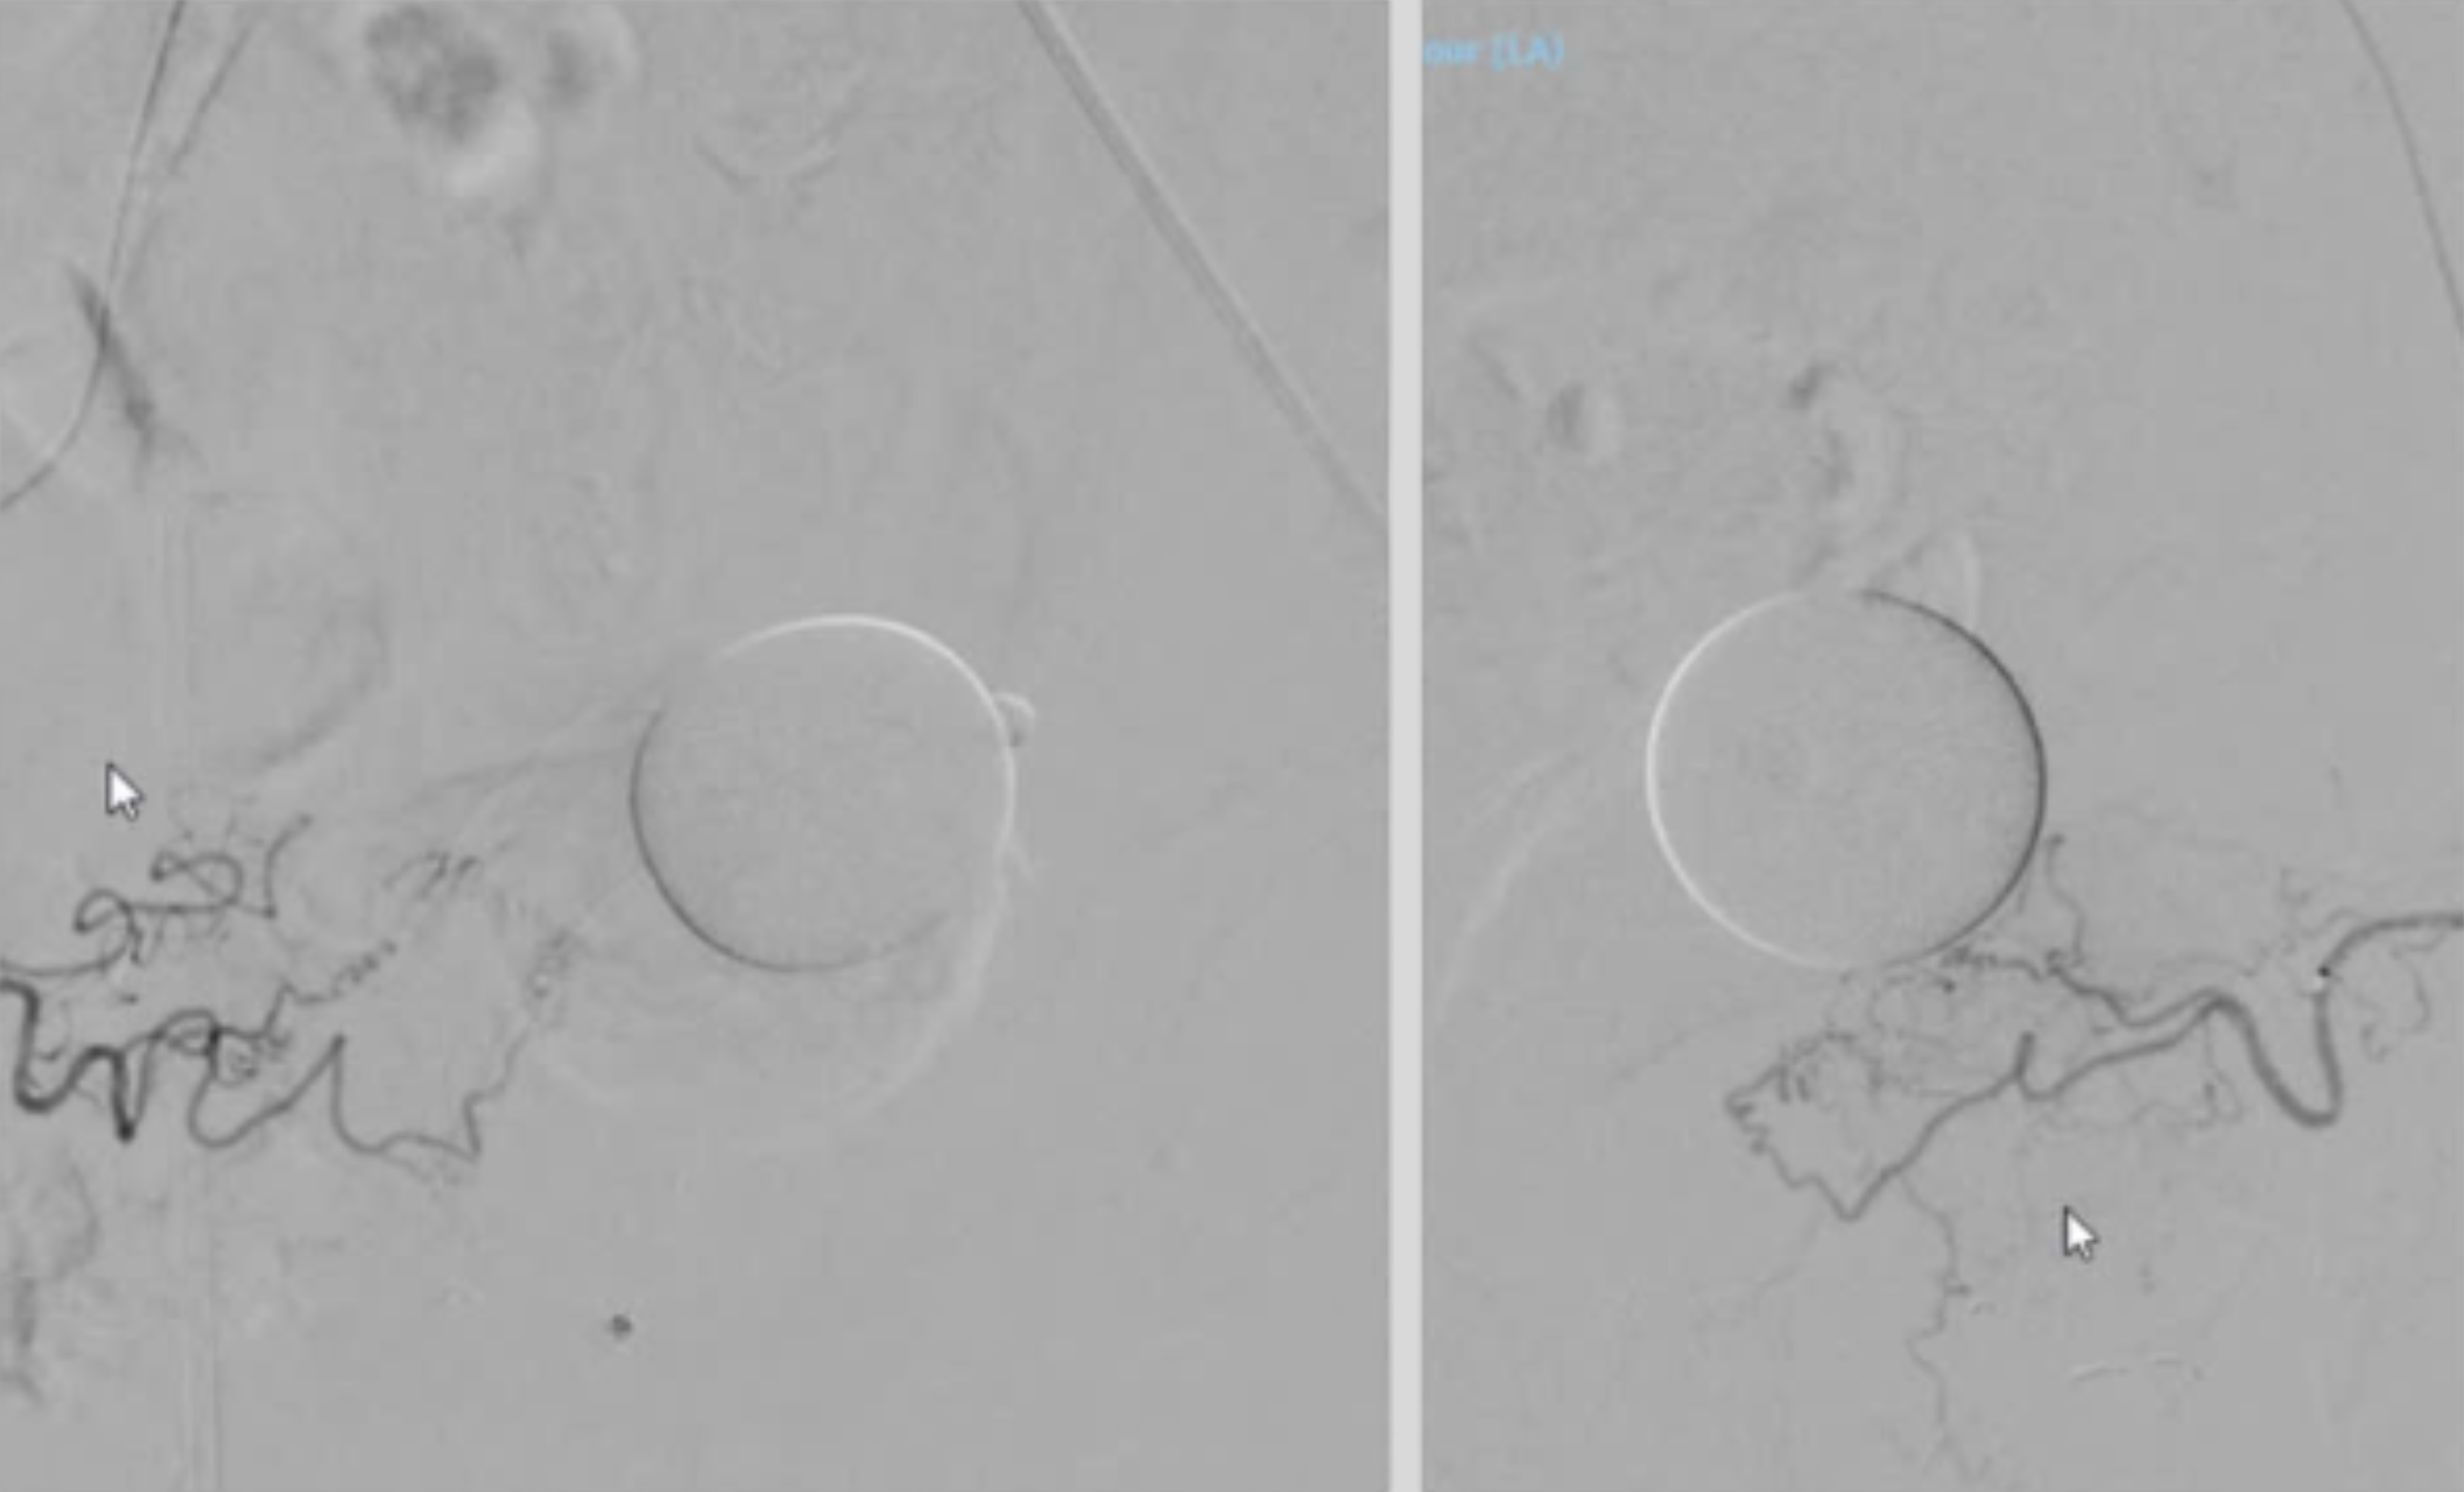

![]() ![]() |

Hình ảnh DSA trước (trái) và sau thủ thuật nút mạch. Động mạch tiền liệt tuyến đã được thuyên tắc hoàn toàn. |